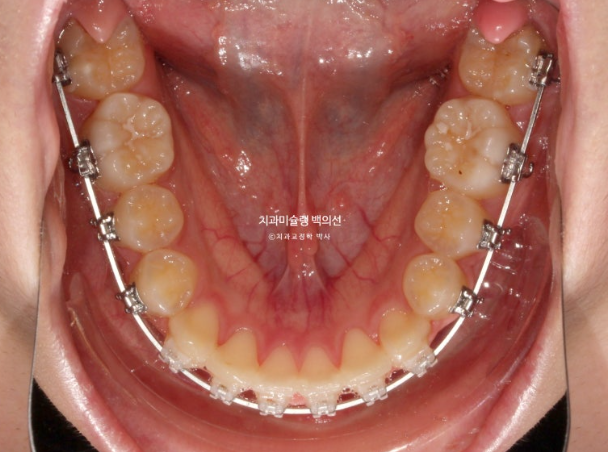

치료시작 2년 3개월차, 드디어 치료를 마무리 합니다.

25.05

중심선은 잘 맞으며 교합은 깔끔합니다.

위에만 작은어금니를 발치하면 교합이 괜찮나요?

하는 질문을 많이 하십니다.

상악만 발치교정 결과 교합은 이러합니다.